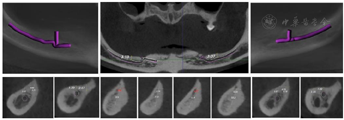

影像学检查:余留牙牙根形态完整,缺牙区域牙槽嵴严重萎缩,骨高度和骨宽度均不足,骨质未见明显异常(图8)。

术前拍摄CBCT、口外、口内临床照片,进行种植位点分析与牙槽骨测量,从CBCT图像可见余留牙牙根形态完整,缺牙区域牙槽嵴严重萎缩,骨高度和骨宽度均不足,骨质未见明显异常,且下颌神经前环以及和下颌切牙管位置表浅,常规种植位点无法支持种植固定义齿修复(图9)。

将CBCT的DICOM数据转为STL格式后获得数据模型,找到下颌切牙管前端A,颏孔C,和A与C曲线的中点B,在A点和B点设置两颗固位钉,联合颏孔C形成下颌切牙管指示定位导板(图11,图12,图13,图14,图15)。